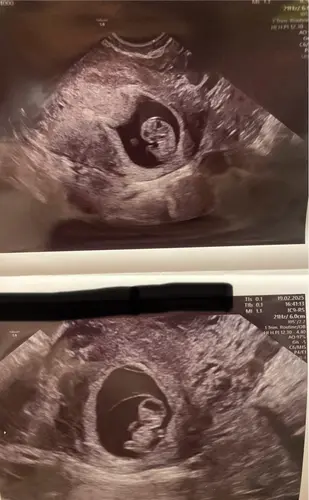

Iemand een gokje echo is op 12w3d geweest :) donderdag nipt test doen :)

Geduldig op de nipt uitslag aan het wachten, wat zou het zijn… 🎀 of 💙